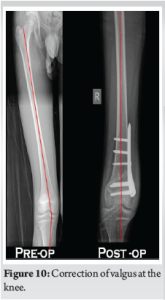

The valgus at the knee was corrected to neutral alignment (Fig. 10). The mechanical lateral distal femoral angle was corrected from 81° to 88° post-operatively. The trochleoplasty had increased the trochlear depth from 1.2 to 4 mm and the sulcus angle from 172° to 140° postoperatively (Fig. 11). The patient is currently at 1 year follow-up, and has attained full range of motion (Fig. 12). There has been no further episodes of patellar dislocation and the patient is leading an active lifestyle without apprehension or instability. The Tegner Lysholm knee score improved from a pre-operative value of 51 to a post-operative value of 94, and the Kujala knee score also showed improvement from 18 to 27 postoperatively (Fig. 13).